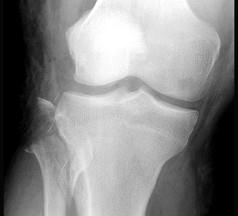

问题 25岁男性,摩托车撞伤右膝外侧,X线片如图,考虑为腓骨小头骨折,检查发现踝关节不能主动背伸,可能并发 ( )

选项 A、腓总神经损伤 B、腓骨长、短肌撕裂伤 C、胫神经损伤 D、坐骨神经损 E、伤胫前肌撕裂伤

答案 A